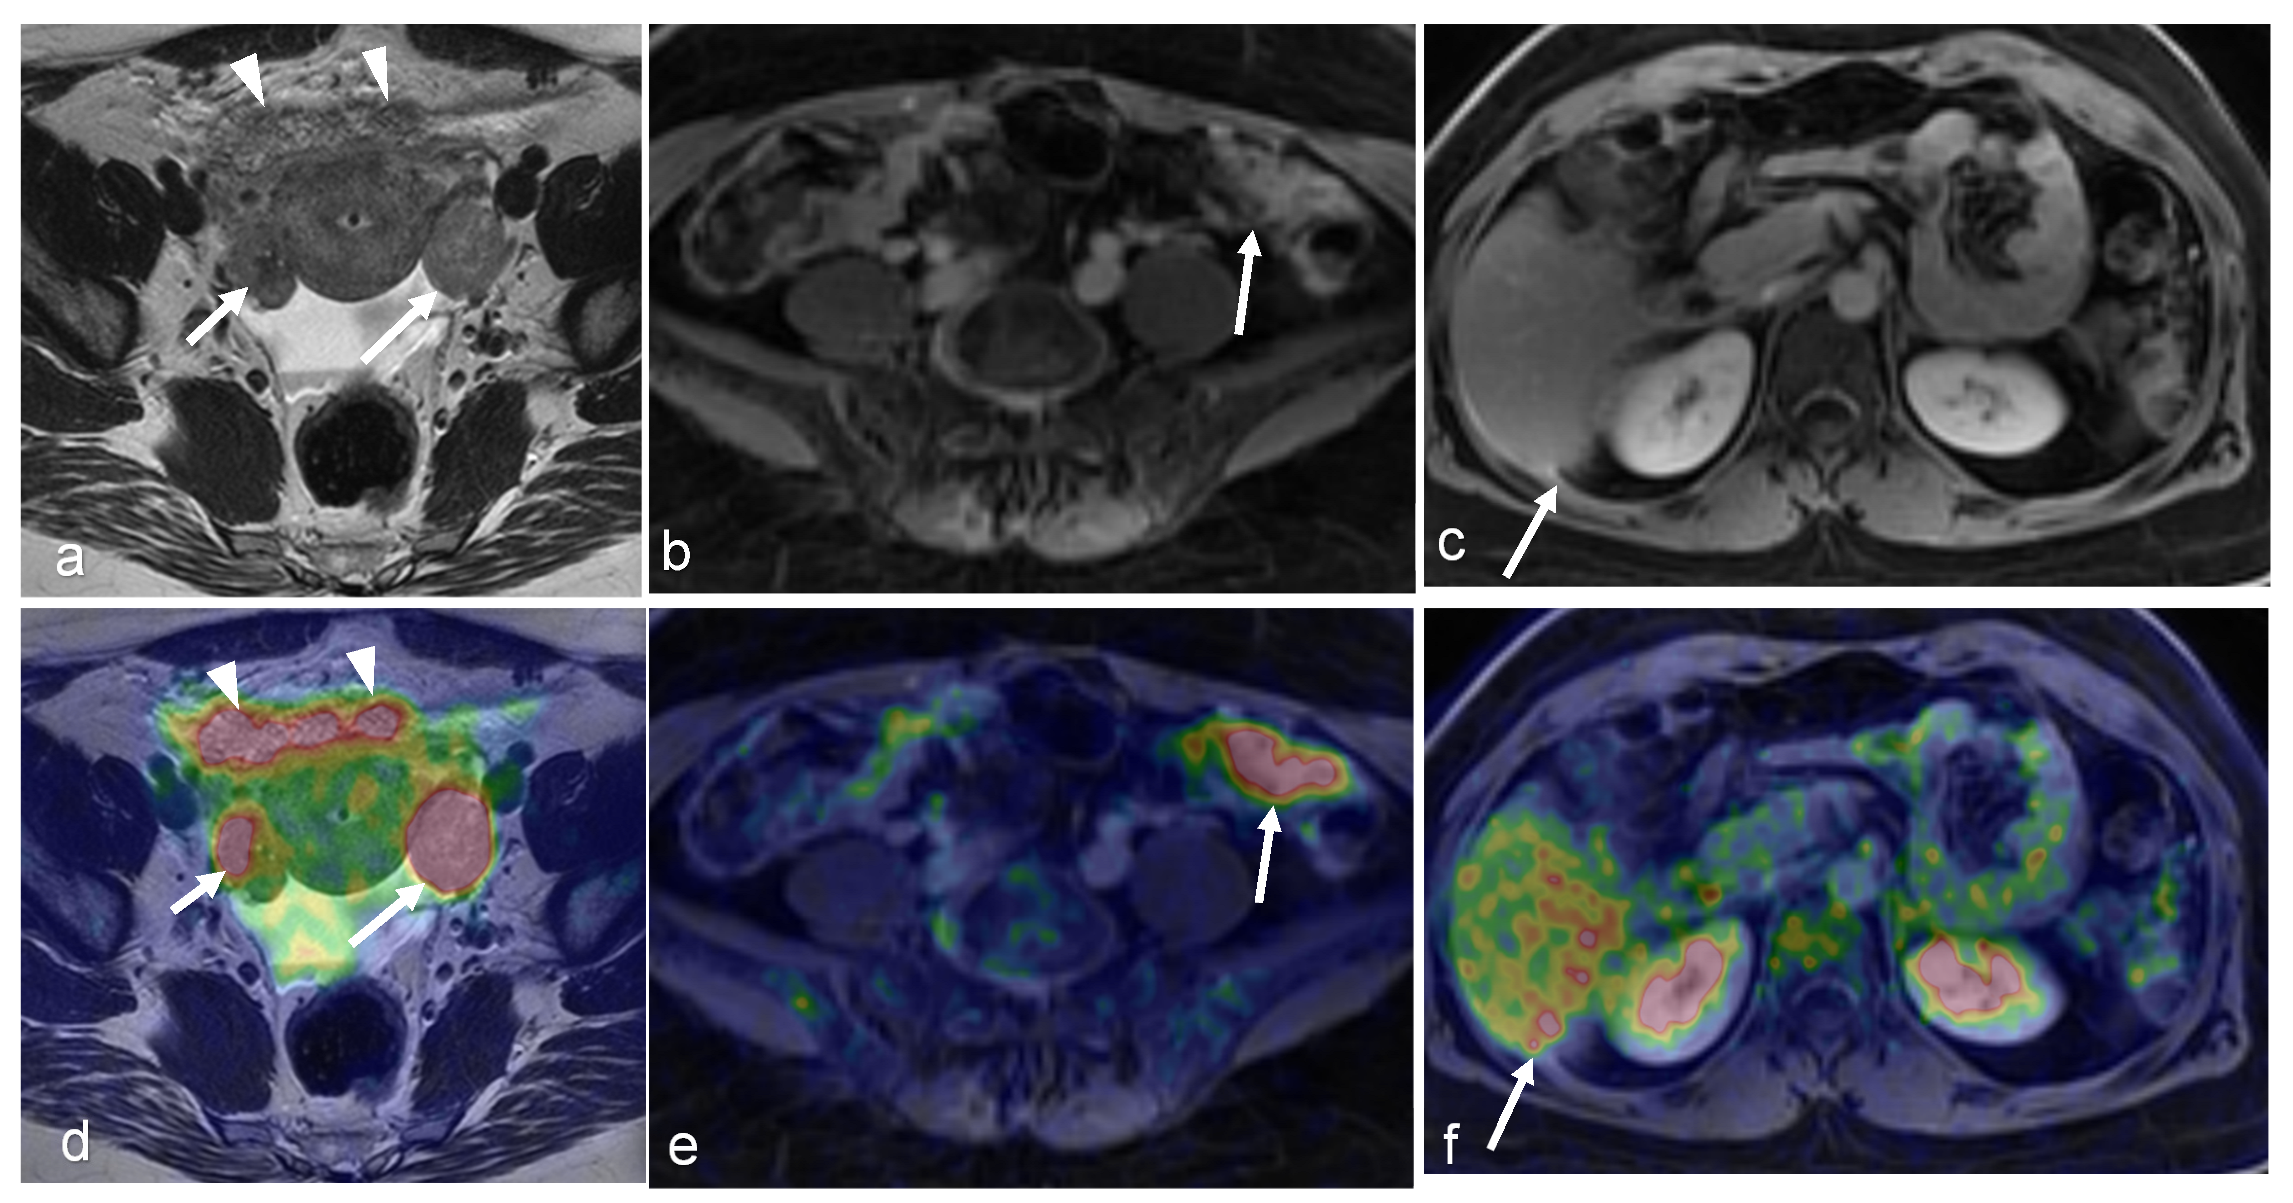

3.2. Endometrial Cancer

- Tsuyoshi, H.; Tsujikawa, T.; Yamada, S.; Chino, Y.; Shinagawa, A.; Kurokawa, T.; Okazawa, H.; Yoshida, Y. FDG-PET/MRI with high-resolution DWI characterises the distinct phenotypes of endometrial cancer. Clin. Radiol. 2020, 75, 209–215. [Google Scholar] [CrossRef] [PubMed]

- Tsuyoshi, H.; Tsujikawa, T.; Yamada, S.; Okazawa, H.; Yoshida, Y. Diagnostic value of 18F-FDG PET/MRI for staging in patients with endometrial cancer. Cancer Imaging 2020, 20, 75. [Google Scholar] [CrossRef]

- Kitajima, K.; Suenaga, Y.; Ueno, Y.; Kanda, T.; Maeda, T.; Takahashi, S.; Ebina, Y.; Miyahara, Y.; Yamada, H.; Sugimura, K. Value of fusion of PET and MRI for staging of endometrial cancer: Comparison with ¹⁸F-FDG contrast-enhanced PET/CT and dynamic contrast-enhanced pelvic MRI. Eur. J. Radiol. 2013, 82, 1672–1676. [Google Scholar] [CrossRef]

- Ironi, G.; Mapelli, P.; Bergamini, A.; Fallanca, F.; Candotti, G.; Gnasso, C.; Taccagni, G.L.; Sant’Angelo, M.; Scifo, P.; Bezzi, C.; et al. Hybrid PET/MRI in Staging Endometrial Cancer: Diagnostic and Predictive Value in a Prospective Cohort. Clin. Nucl. Med. 2022, 47, e221–e229. [Google Scholar] [CrossRef]

- Shih, I.L.; Yen, R.F.; Chen, C.A.; Chen, B.B.; Wei, S.Y.; Chang, W.C.; Sheu, B.C.; Cheng, W.F.; Tseng, Y.H.; Chen, X.J.; et al. Standardized uptake value and apparent diffusion coefficient of endometrial cancer evaluated with integrated whole-body PET/MR: Correlation with pathological prognostic factors. J. Magn. Reson. Imaging 2015, 42, 1723–1732. [Google Scholar] [CrossRef] [PubMed]

- Nakamura, K.; Joja, I.; Fukushima, C.; Haruma, T.; Hayashi, C.; Kusumoto, T.; Seki, N.; Hongo, A.; Hiramatsu, Y. The preoperative SUVmax is superior to ADCmin of the primary tumour as a predictor of disease recurrence and survival in patients with endometrial cancer. Eur. J. Nucl. Med. Mol. Imaging 2013, 40, 52–60. [Google Scholar] [CrossRef] [PubMed]